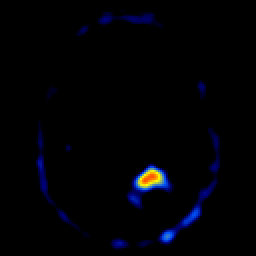

glioma overlay -- Slice #18

[Home][Help][Clinical] Slice 18